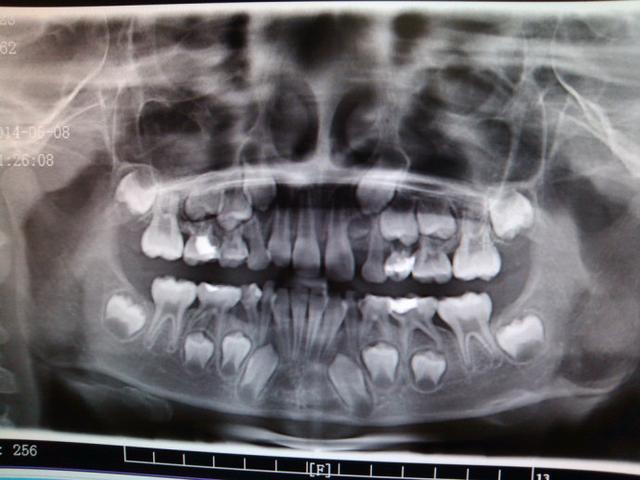

2、接近替换的松动乳牙:乳牙牙根已明显吸收,恒牙还没萌出,如果此时乳牙的牙髓感染已不宜治疗,只能拔除。可以根据孩童的同名牙的更换情况,年龄及X线片来做相应的判断。